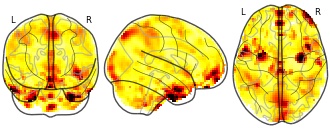

Affect Label: Amyg Connectivity, Label - Blur: con 0002

License information was derived automaticallyDescriptionContrast 2: bl

Collection description

Neurodevelopmental Changes Across Adolescence in Viewing and Labeling Dynamic Peer Emotions

Adolescence is a sensitive period of social-affective development, characterized by biological, neurological, and social changes. The field currently conceptualizes these changes in terms of an imbalance between systems supporting reactivity and regulation, specifically nonlinear changes in reactivity networks and linear changes in regulatory networks. Previous research suggests that the labeling or reappraisal of emotion increases activity in lateral prefrontal cortex (LPFC), and decreases activity in amygdala relative to passive viewing of affective stimuli. However, past work in this area has relied heavily on paradigms using static, adult faces, as well as explicit regulation. In the current study, we assessed cross-sectional trends in neural responses to viewing and labeling dynamic peer emotional expressions in adolescent girls 10-23 years old. Our dynamic adolescent stimuli set reliably and robustly recruited key brain regions involved in emotion reactivity (MOFC/vMPFC, bilateral amygdala) and regulation (bilateral dorsal and ventral LPFC). However, contrary to the age-trends predicted by the dominant models in studies of risk/reward, the LPFC showed a nonlinear age trend across adolescence to labeling dynamic peer faces, whereas the MOFC/vMPFC showed a linear decrease with age to viewing dynamic peer faces. There were no significant age trends observed in the amygdala.Subject species

homo sapiens

Map type

Other